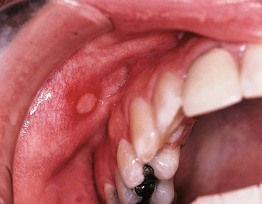

• Minor aphthae (most frequent form): painful, round to ovoid, shallow ulcers that are usually <5 mm in diameter; feature a yellowish-white to gray pseudomembranous base, well-defined border, and prominent erythematous rim (Fig. 59.10); favor the buccal or labial mucosa and typically heal in 1–2 weeks without scarring.

Fig. 59.10 Recurrent aphthous stomatitis. Shallow, creamy-white ulceration surrounded by an intensely red halo and located on nonkeratinized mucosa, representing a classic presentation. Courtesy, Carl M. Allen, MD, and Charles Camisa, MD.